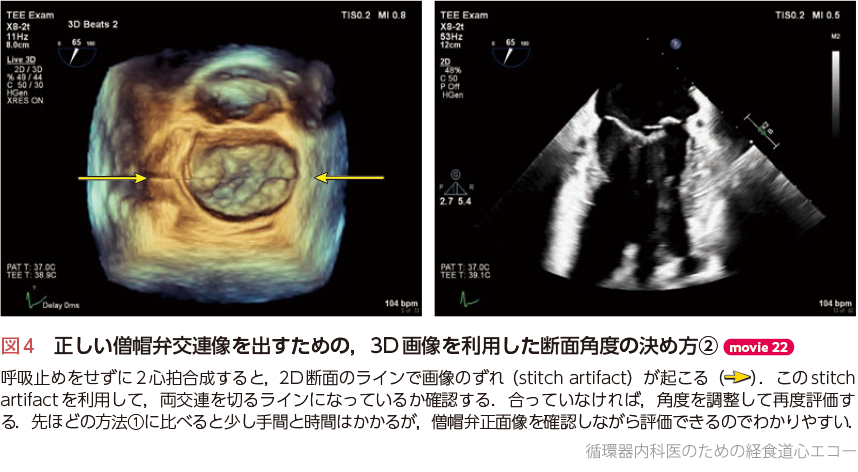

初心者から研修医向けの経食道心エコーに関する専門書。- タイトル: 経食道心エコー II- 監修: 野村 実- 定価: 12,500円ご覧いただきありがとうございます。数回読んだだけで非常にきれいな状態です。